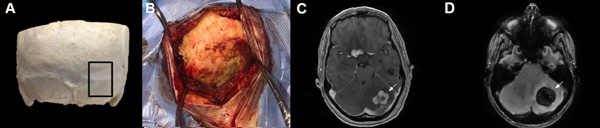

El abordaje suboccipital paramediano (ASOPM) es generalmente utilizado para el tratamiento de lesiones que afectan un hemisferio cerebeloso, en las cuales no es necesario exponer la línea media o la región del ángulo pontocerebeloso. Las lesiones para las cuales se indica este abordaje pueden ser de origen tumoral (metástasis, hemangioblastomas, etc), fenómenos hemorrágicos, isquémicos o malformaciones vasculares (MAVs, cavernomas)1-3 (Fig 1 C-D). Distintas incisiones pueden ser utilizadas para exponer el hueso occipital y realizar la craneotomía, ubicándose estas por convención en el punto medio entre la línea inion-mastoides, variando su ubicación dentro del tercio medio de dicha línea dependiendo de la ubicación exacta de la patología a tratar. El tamaño de la incisión y la craneotomía están determinados por la patología, requiriendo en algunos casos una incisión pequeña y una craneotomía centrada en el hueso occipital o, en casos de lesiones voluminosas, una incisión mayor con una craneotomía generosa que se extienda al foramen magno2-3. En tales casos, al no poder realizarse una disección por planos de los músculos de la nuca, ya que el abordaje exige un trayecto transmuscular, y no contar con reparos óseos constantes (Fig 1 A-B), la disección en dirección a la unión craneocervical (UCC) puede comprometer el segmento V3 de la arteria vertebral (sV3-AV). Este escenario contrasta con el de los otros abordajes a la región suboccipital que contienen reparos óseos constantes, como la apófisis mastoides y el segmento vertical de la línea nucal inferior en el abordaje retrosigmoideo4, o aquellos que conllevan incisiones de mayor tamaño como el abordaje extremo lateral transcondilar (ELITE) o el abordaje far lateral, donde una mayor exposición de la región permite la identificación de distintos reparos utilizados para proteger el sV3-AV (como el arco posterior de C1, la apófisis transversa de C1, la línea atlanto mastoidea, el tejido adiposo del triángulo suboccipital, la arteria de Salmon y el plexo venoso suboccipital de Zolani). 5-13

Figura 1. A. Se señala en un cráneo la región anatómica donde se centra el ASOPM, evidenciando la falta de reparos óseos. B. Imagen quirúrgica de un ASOPM donde se puede ver la falta de referencias anatómicas constantes. C. RMN con contraste EV donde se puede ver una LOE tumoral en el sector medio del hemisferio cerebeloso izquierdo. D. RMN que evidencia una lesión vascular (cavernoma) ubicado en el tercio medio del hemisferio cerebeloso izquierdo.